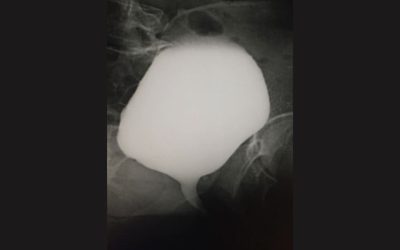

Cystographie

La cystographie est un examen radiographique (utilisant des rayons X) permettant d’explorer la vessie les uretères, après l’injection d’un produit à base d’iode.